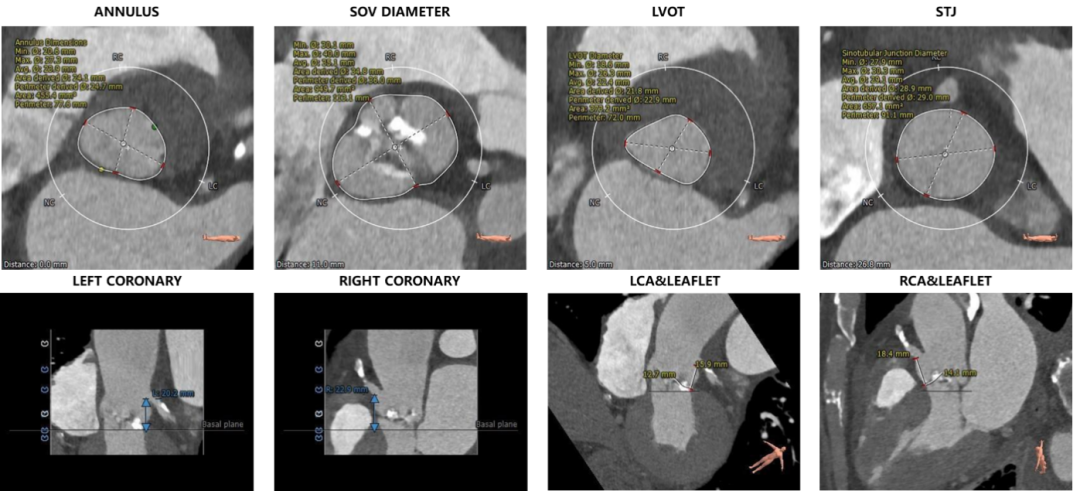

主动脉根部评估:

瓣环上解剖结构评估: